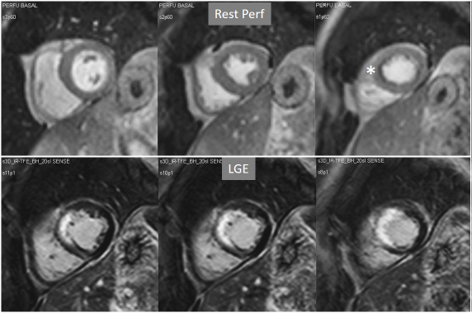

Particularly important, in practice, is the issue of perfusion studies in patients with previous MI. In theory, a basal rest perfusion study should exhibit a reduced signal intensity in the infarcted area, as is the case in the acute phase of a large transmural MI (Fig. 14A). However, not infrequently, the presence and extent of a rest perfusion defect does no correlate with the actual area of necrosis in either, acute (Fig. 14B) or chronic MI (Fig. 15). Signal intensity in areas of previous MI is thus, not dependent merely on the presence of scar tissue, but some other factors lead to differences in CA concentration between MI and remote regions and, in this sense, rest perfusion CMR cannot be equated to SPECT studies, where rest defects are directly related to the presence of infarcted myocardial tissue not amenable to radiotracer uptake [45].

Fig. 14.Rest perfusion after acute myocardial infarction. (A) Frames from different sequences in a case of acute MI showing, from left to right, (1) gross transmural defect at the rest perfusion study (arrow); (2) signs of regional myocardial edema at STIR T2, with a mid-line low intensity region which proves to be due to (3) intramural hematoma at T2* sequence; (4) persistence of hypoperfusion at Early Gadolinium Enhancement (EGE); and (5) transmural anteroseptal necrosis with a subendocardial area of microvascular obstruction (arrow). (B) The same series of sequences in another patient with AMI showing (1) mild subendocardial defect at rest (arrow); (2) regional edema; (3) absence of hematoma at T2*; (4) lack of persistent defect at EGE; and, finally, (5) a transmural infero-lateral LGE (arrow) without microvascular obstruction.